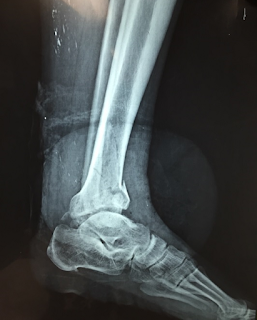

Idx: Ruptura de tendón supraespinoso derecho

-Radiografía McNab y su utilidad en lesiones manguito rotador